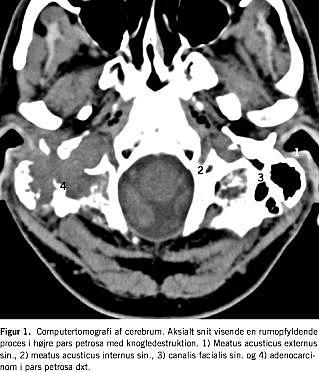

Ved udredning hos en praktiserende otolog blev der fundet let påvirkning af balancenerven på højre side. Ni måneder efter symptomdebuten indlagdes patienten med komplet højresidig perifer facialisparese og tiltagende smerter i højre ansigtshalvdel og øre ledsaget af våd knitren ved tygning. De øvrige kranienerver var upåvirkede. En lumbalpunktur afkræftede neuroborreliose. Ved en objektiv undersøgelse blev der fundet palpationsømhed over højre processus mastoideus. Ved otoskopi fandtes let rødme og hævelse af øregangens loft og bagvæg samt let inflammeret trommehinde med frembuling over flaccidaregionen. En audiometri viste mindre asymmetrisk høretab med overvægt i diskanten på højre side og speech reception threshold (SRT) på 5/0 dB. Ved en magnetisk resonans-skanning blev der påvist væskesignal i højre mastoid med opladning i pars petrosa. Ved en computertomografi blev der påvist en bløddelstumor i højre pars petrosa med knogledestruktion (Figur 1 ). En biopsi fra tumor viste middelhøjt differentieret adenokarcinom. Ved en positronemissionstomografi blev der påvist en 4 × 4 cm stor tumor i højre pars petrosa med relation til og mulig indvækst i cerebellum, og der var mistanke om højresidig angulær glandelmetastase. En helkropsskanning gav ikke mistanke om en primær tumor uden for pars petrosa. Tumoren fandtes inoperabel og patienten blev henvist til stråleterapi.